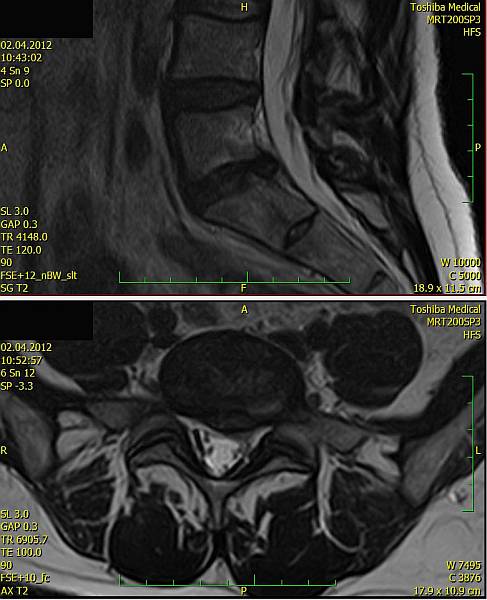

1. Žena, 48 let. Na MR patrná 8mm velká paramediální hernie L5/S1 vlevo s extruzí materiálu ploténky do epidurálního prostoru a útlakem kořenů L5 a S1 vlevo. Pacientce byla doporučena operace, kterou odmítla a zvolila alternativní postup s aplikací ozonu. Viz obr. 6a

Na kontrolním MR po 1 měsíci (po 2 aplikacích ozonu) periradikulárně je viditelné vymizení fragmentů v epidurálním prostoru a částečná retrakce meziobratlové ploténky. Subjektivně výrazná úleva, po 4 týdnech návrat do práce. Viz obr. 6b